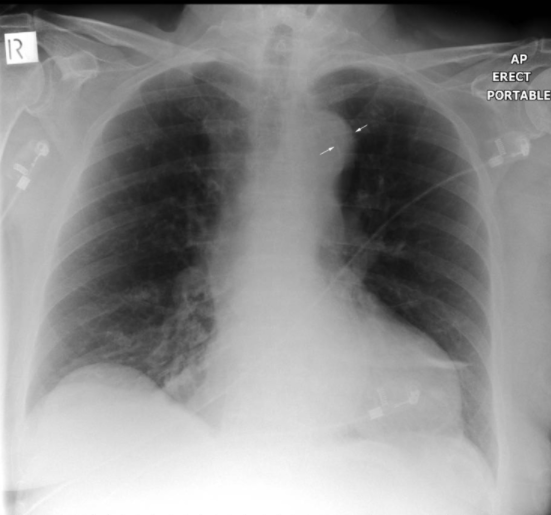

【カルシウムサインの一例その2】

Calcium Sign – wikiRadiography

【カルシウムサインの一例その3】